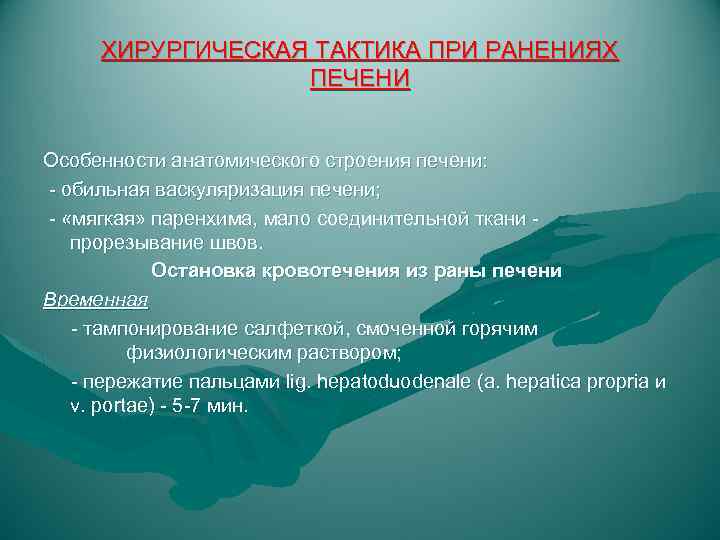

ХИРУРГИЧЕСКАЯ ТАКТИКА ПРИ РАНЕНИЯХ ПЕЧЕНИ Особенности анатомического строения печени: - обильная васкуляризация печени; - «мягкая» паренхима, мало соединительной ткани прорезывание швов. Остановка кровотечения из раны печени Временная - тампонирование салфеткой, смоченной горячим физиологическим раствором; - пережатие пальцами lig. hepatoduodenale (a. hepatica propria и v. portae) - 5 -7 мин.

ХИРУРГИЧЕСКАЯ ТАКТИКА ПРИ РАНЕНИЯХ ПЕЧЕНИ Особенности анатомического строения печени: - обильная васкуляризация печени; - «мягкая» паренхима, мало соединительной ткани прорезывание швов. Остановка кровотечения из раны печени Временная - тампонирование салфеткой, смоченной горячим физиологическим раствором; - пережатие пальцами lig. hepatoduodenale (a. hepatica propria и v. portae) - 5 -7 мин.